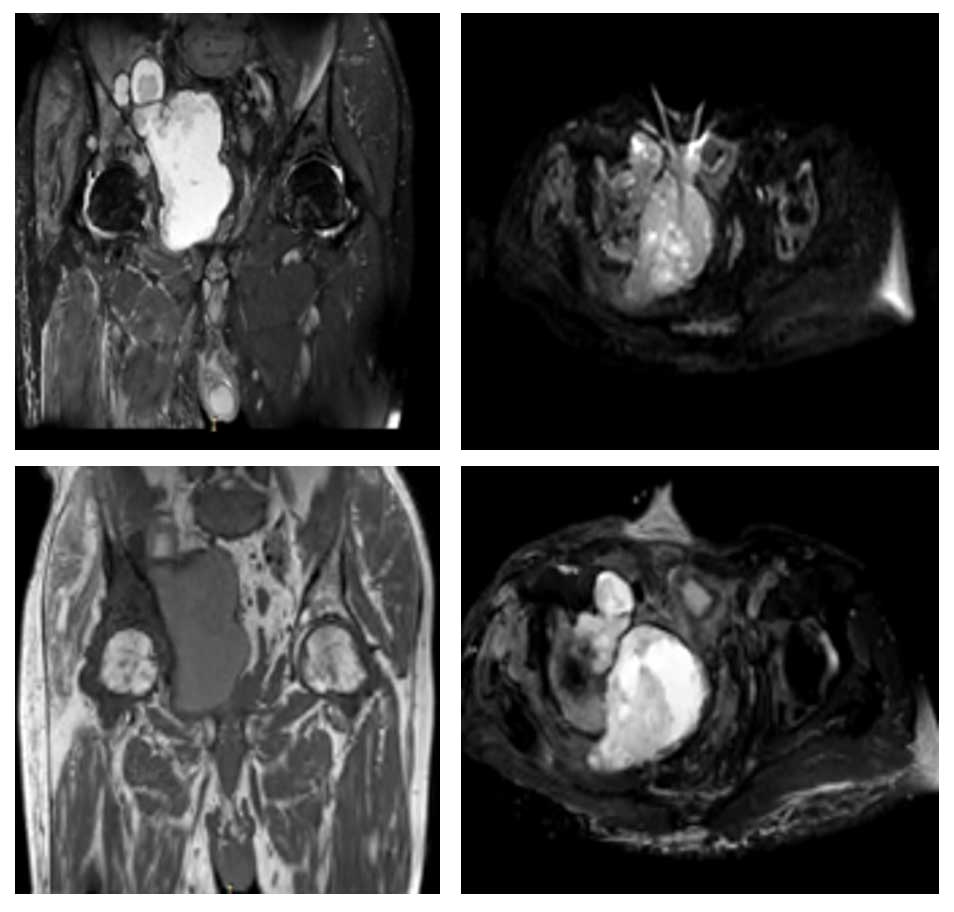

Ameliyat Öncesi: MR’da kemik harabiyetine eşlik eden büyük tümör dokusu görülmekte.